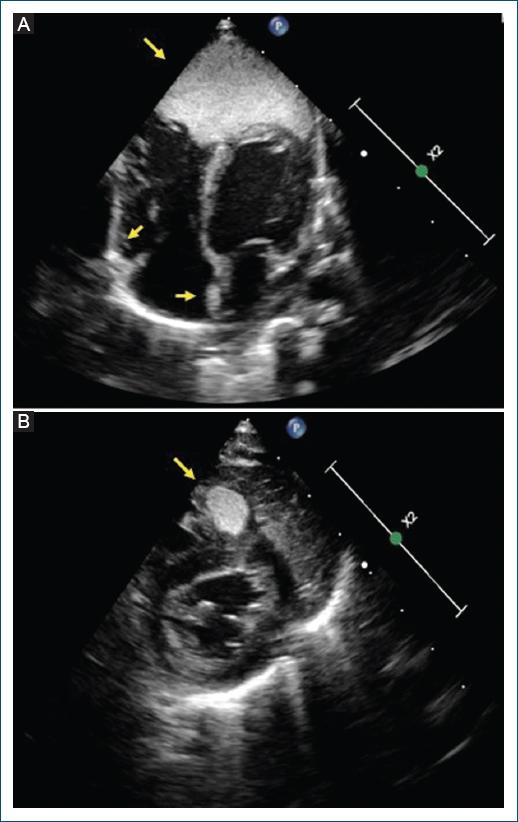

Recién nacida que ingresó para estudio por diagnóstico prenatal de múltiples masas corticales. Se realizó un electrocardiograma que mostró un ascenso del segmento ST en las derivaciones anterolaterales e inferiores, con descenso del ST en las derivaciones I, aVL, V1 y V2 (Fig. 1). El complejo QRS presentaba amplios voltajes, sugestivos de hipertrofia ventricular, sin ondas Q patológicas. Se realizó un ecocardiograma (Fig. 2) que evidenció diversas masas homogéneas hiperecoicas en el tabique interauricular, el ventrículo derecho y el ápex del ventrículo izquierdo, compatibles con rabdomiomas, siendo este último gigante. No presentaba alteraciones de la contractilidad segmentaria y la fracción de eyección estaba preservada. La monitorización continua no registró eventos arrítmicos. El estudio sistémico reveló tuberomas corticales y quistes subependimarios, así como un angiomiolipoma renal, lo que llevó al diagnóstico de complejo de esclerosis tuberosa. La paciente fue manejada de forma conservadora y dada de alta sin incidencias clínicas, programando un seguimiento estrecho multidisciplinario.

Figura 2 Ecocardiograma transtorácico. A: plano apical de cuatro cámaras. B: plano paraesternal eje corto.